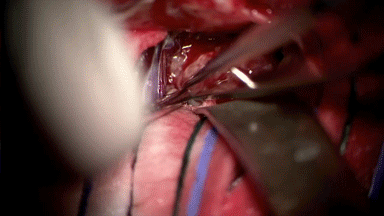

枪状镊间断可见黑色的栓塞肿瘤血管

见肿瘤内铸形的栓塞剂(显微剪刀尖部)

小心分离颈内动脉周围肿瘤组织